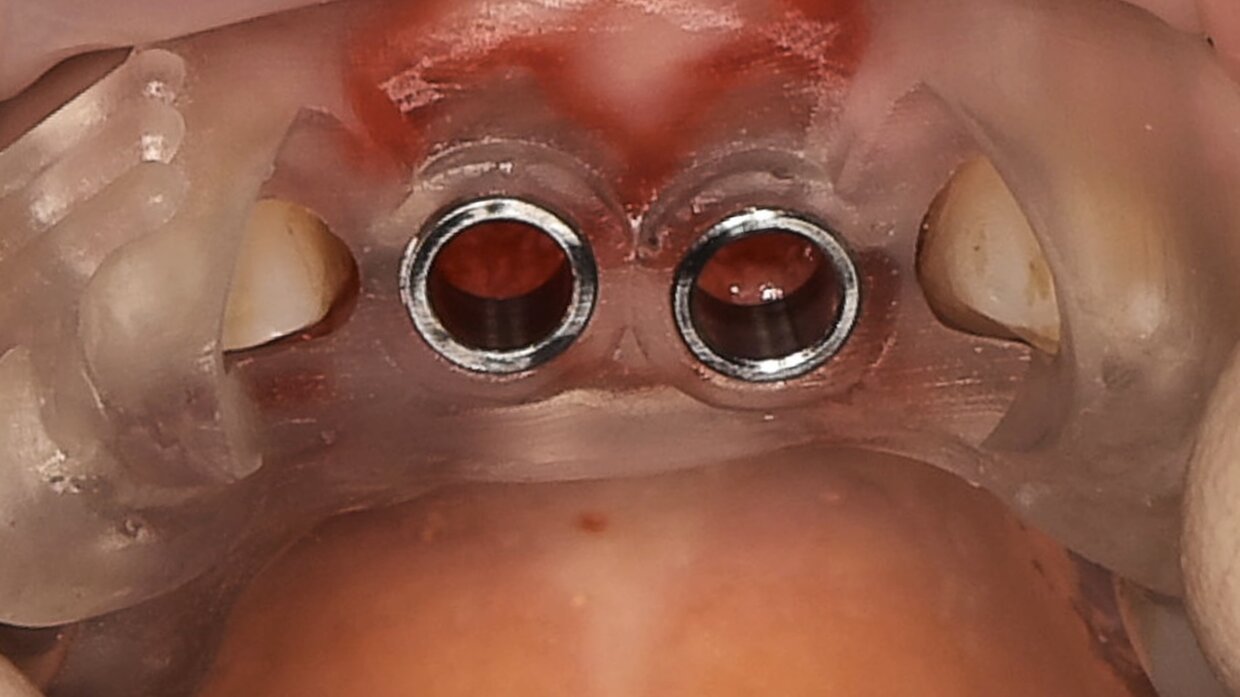

Minimamente invasivo, senza lembo chirurgico nè punti di sutura

Il posizionamento degli impianti è stato pianificato prima dell'intervento su un software dedicato. In un'unica seduta, dopo l'estrazione degli elementi dentari compromessi, sono stati immediatamente inseriti gli impianti nella posizione pianificata, grazie alla realizzazione della dima chirurgica. Per ridurre il riassorbimento osseo a lungo termine e garantire quindi una maggiore resa estetica (vista la zona d'intervento), la chirurgia è stata eseguita con una particolare tecnica denominata: Socket Shield Technique.